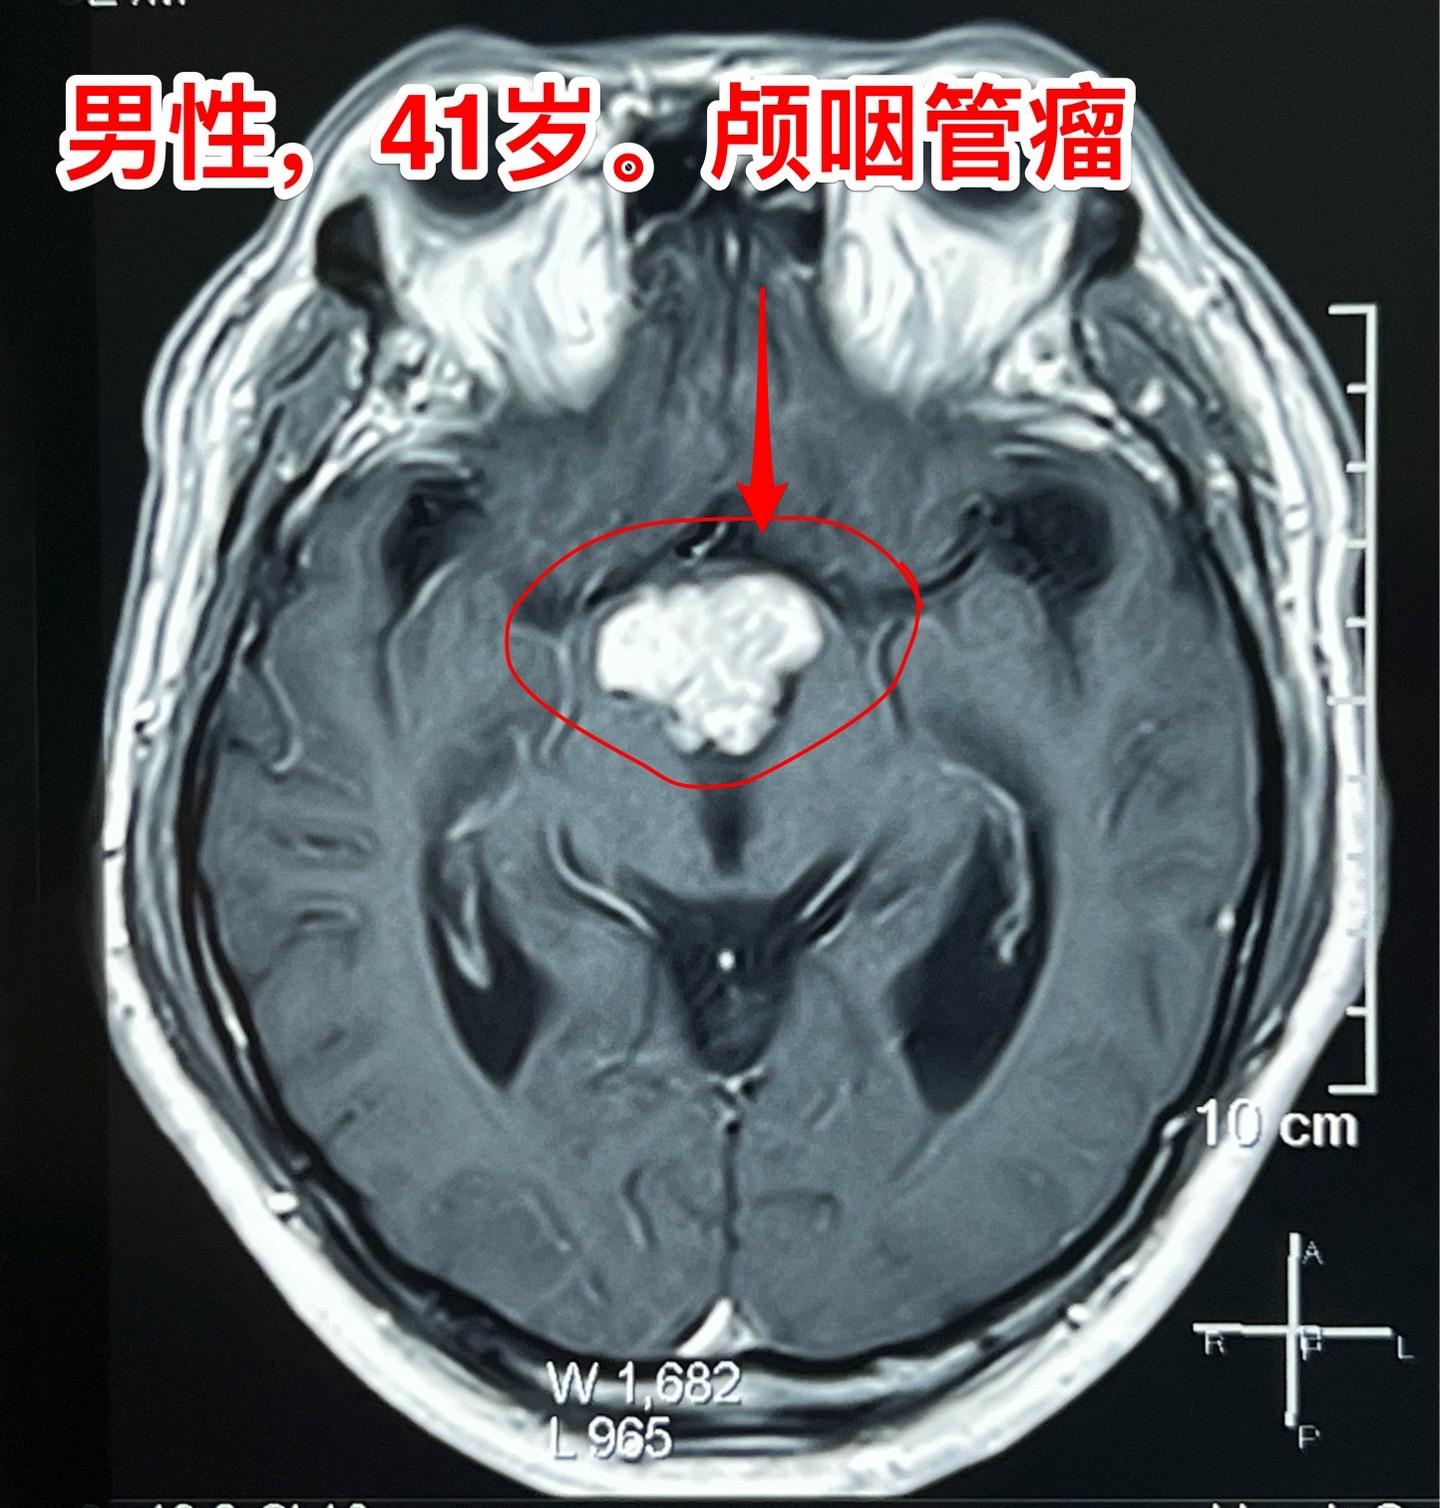

三个月颅咽管瘤直径增加了1厘米。41岁辽宁省沈阳的男性,五个月前因眼前发花到医院检查发现颅咽管瘤,同时期他的一个吉林省的朋友也发现患有颅咽管瘤(吉林省朋友的颅咽管瘤有钙化,2024.1.25在我科作了手术)(沈阳病人的颅咽管瘤没有钙化)。 惧怕手术是人之常情。沈阳患者发现颅咽管瘤后也是害怕作手术的,所以他选择试试中药治疗,到成都某医院去看病,服用中药三个月,到2024年4月复查磁共振显示肿瘤的直径长大了1厘米,同时视力症状也越来越明显,化验激素也出现下降。所以患者就下决心来找我作手术。